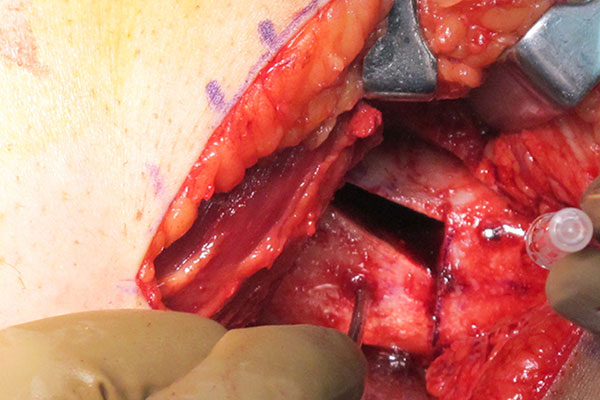

Varising Derotational Distal Femoral Osteotomy